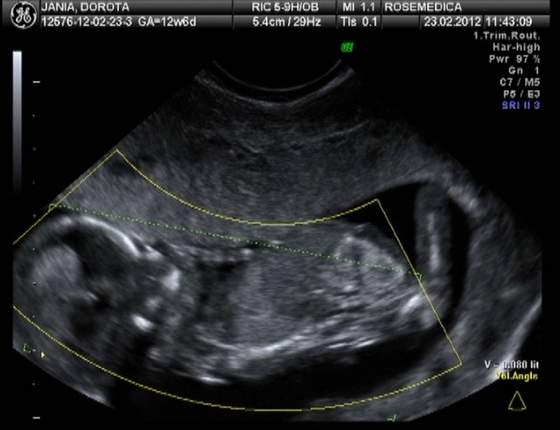

Ja już praktycznie w ryk, ona mówi, że może sprzęt jest już na te wymiary zły, bo ma jakąś tam rozdzielczość i żebym jutro pojechała do szpitala, ale jak zobaczyła, jaka już bliska jestem histerii, zadzwoniła do znajomego lekarza ze szpitala i pojechaliśmy z A od razu. Tam od razu miałam usg genetyczne już przez brzuch i okazało się, że wszystko jest ok :-):-):-) CRL 46 mm -> 11,3 tc

Dziękuję Wam KochaneMoże kiedyś zbiorę się i wytnę kawałek z filmu jak się Dzidzia drapie pogłowie... A to zdjątka (starałam się wybrać jak najlepsze kadry z filmu):

Zobacz załącznik 440449Zobacz załącznik 440450Zobacz załącznik 440451Zobacz załącznik 440452